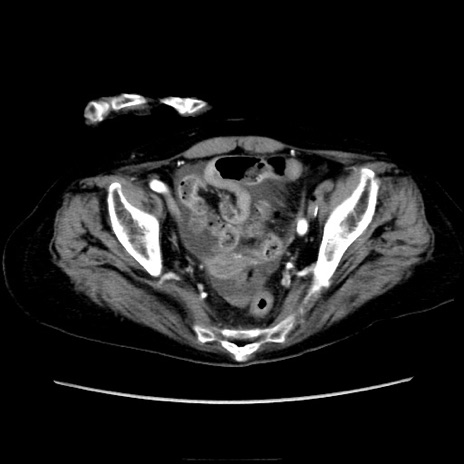

症例40(横断像)

横断像